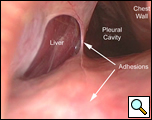

Consultation with general and thoracic surgery services agreed that operative correction was required due to progressive symptoms and partial hepatic vein obstruction. VATS revealed that the right lobe of the liver was entirely in the right chest, the margins of the diaphragmatic defect could not be seen, and there was no hernia sac (Figure 4). The right lung was trapped and there were multiple adhesions present.